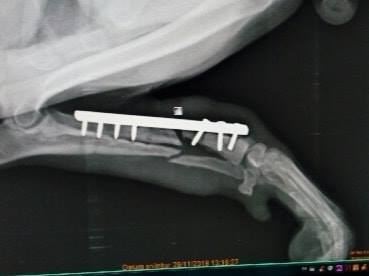

Príbeh Orina

Orin